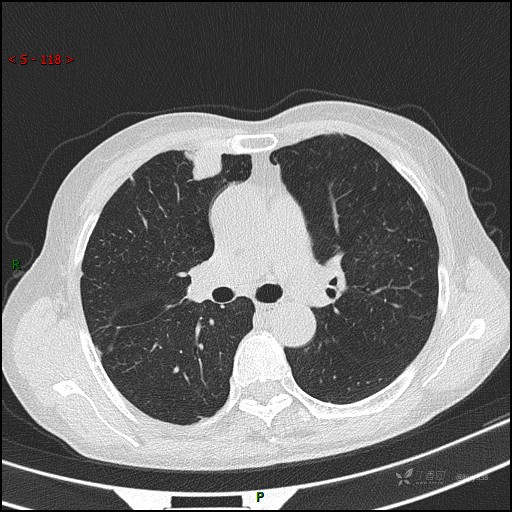

晨读好病例分享|腰痛偶然发现,重在分析,结果公布~

主诉:发现肺部占位4天

简要病史:者4天前因腰痛于当地人民医院就诊,住院期间完善检查,胸部CT提示:左肺上叶及右肺上叶结节,考虑肿瘤性病变可能,建议进一步检查;予以消炎镇痛、活血化瘀、抑酸护胃、营养神经等对症治疗。现患者为求至上级医院进一步治疗,遂来我院,门诊以“肺占位性病变”收入我科。 病程中,患者精神、饮食、睡眠欠佳,大小便如常,体力体重无明显变化。

辅助检查:CT

讨论:病变性质?

胸部CT平扫